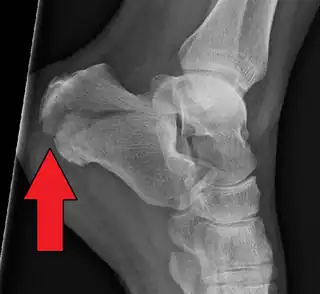

- Fractura de calcáneo.

Hueso calcáneo representado en color rojo.